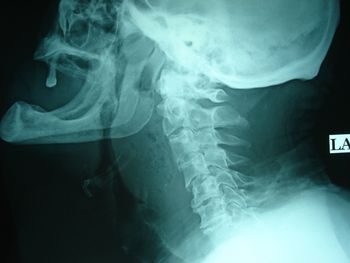

Case history: A 74-year-old male complaining of from difficulty swallowing, fever and neck pain.